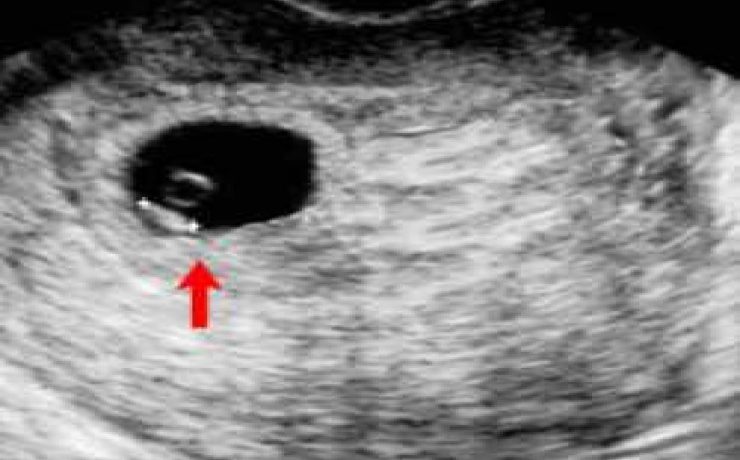

SEGMENTACIÓN HEPÁTICA. EVALUACIÓN ECOGRÁFICA

El hígado se encuentra en el hipocondrio derecho, pesa 1.5 a 2 kg en el adulto y se encuentra mantenido en su posición por la vena cava inferior, las venas suprahepaticas, el ligamento redondo del hígado y los ligamentos coronales y triangulares. Viendo al hígado de manera anterosuperior, se divide